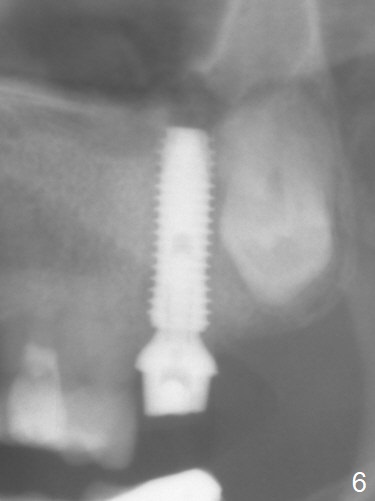

Extraction of the tooth #15 with short clinical crown (suggesting bruxism, Fig.1) reveals a vertical root fracture (Fig.2 <). It seems unnecessary and difficult to create osteotomy in the mesial slope. What can be done is to place starter and 2 mm drills as mesial as possible (Fig.3 (red dashed line: sinus floor). After use of Lindamann bur to move the osteotomy mesially and sequential osteotomy until 3.8x18 mm, a 4.5 mm tap is inserted with clearance from the impacted tooth #16 (Fig.4). A 5x15 mm implant is placed with >60 Ncm with clearance from the 3rd molar (Fig.5,6). If the impacted tooth were removed, the primary stability is expected to be reduced. Impression is taken 6 months postop with 19/20 implants (Fig.7). The bone graft remains in the crestal area immediately and 11 months post cementation (Fig.8,9 *). In the other word, new crestal bone forms after extraction.